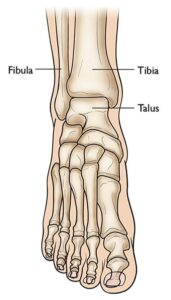

Anatomy of the Ankle Joint

The lower leg consists of two primary bones:- Tibia: Commonly referred to as the shinbone, it is the larger and more prominent bone of the lower leg.

- Fibula: A slender, smaller bone that runs parallel to the tibia.

The three bones that come together to form the ankle joint.